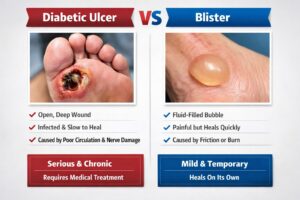

Introduction: A Small Wound That Becomes a Big Problem You notice something on your foot. It might be a blister...

What Is a Plantar Ulcer? (And Why You Shouldn’t Ignore It) A plantar ulcer is an open wound or sore...